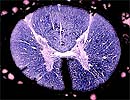

Médula Espinal

y Canal Raquídeo

Corte Transversal